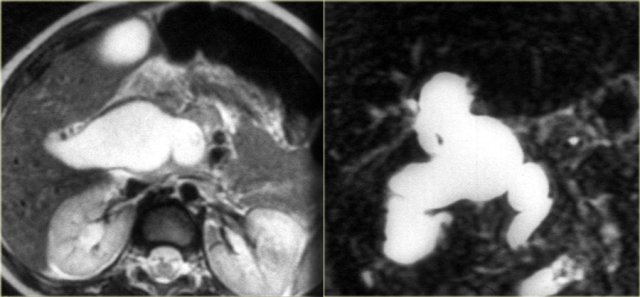

On the left a MRCP in a patient demonstrating a stricture at the level of the hilum.

On MRCP this stricture looked long and worriesome for cholangiocarcinoma.

However, on the ERCP, the ducts have been distended with contrast and we can see that this is a short stricture compatible with the diagnosis of PSC.

During follow up this proved to be just PSC.